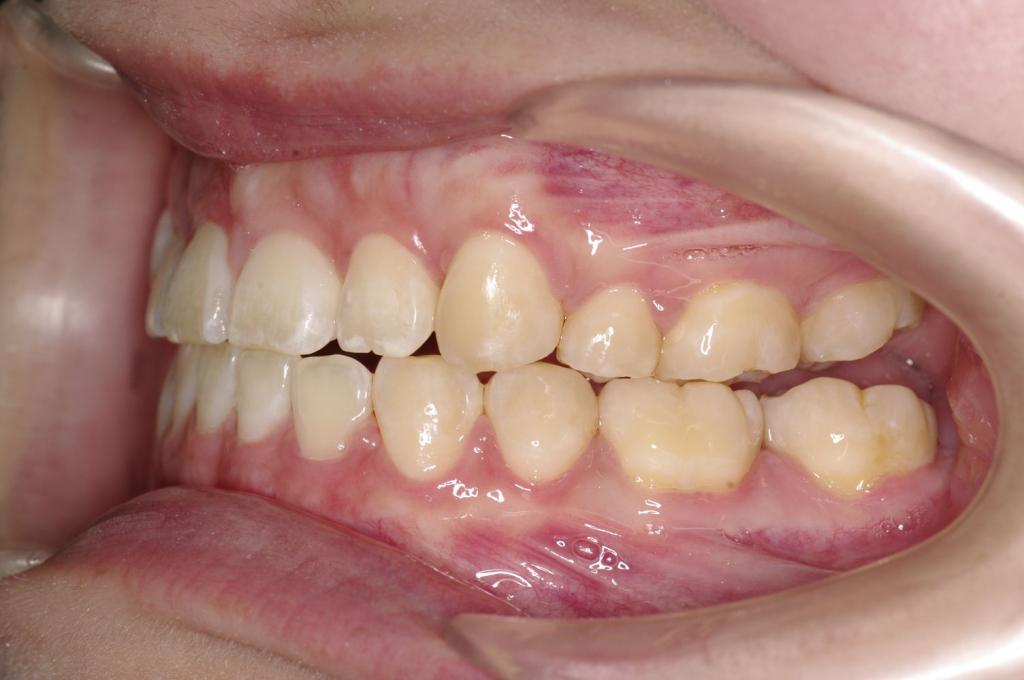

前歯、出っ歯・開咬の矯正治療

(治療期間、治療前後写真、治療方法、費用)WORKS